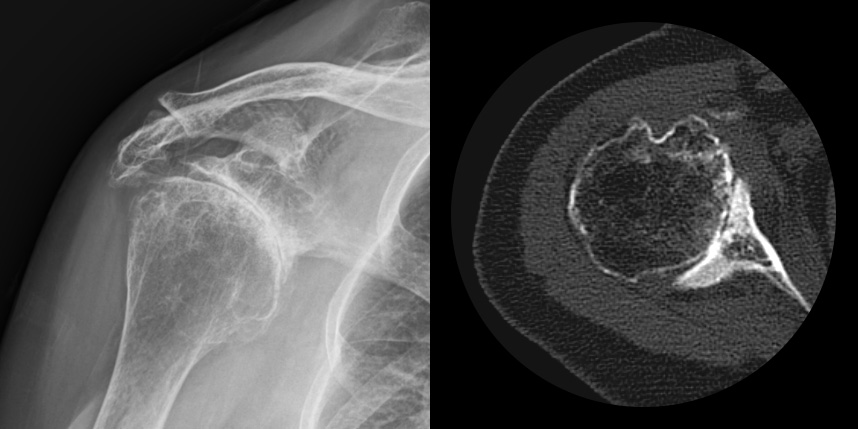

어깨 퇴행성은 많이 써서 닳고 노화에 따른 변화가 생긴 것으로, 말 그대로 어깨가 많이 사용되면서 연골이 닳아서

마모돼어 생기는 관절염입니다. 어깨 회전근개 관절병증 원인으로는 어깨 힘줄 파열을 방치했을 때 관절이 틀어진 상태에서 계속

사용하게 되면 관절이 많이 상해서 관절염까지 진행되며, 이런 경우 회전근개파열의 결과로 생긴 관절병이라고 합니다.

최근에 퇴행성 관절염, 류마티스 관절염 이외에도 많은 환자가 발생하고 있습니다.

발생부위와 원인으로는 퇴생성, 골절이나 탈구 등 외상의 합병증, 류마티스, 진행된 회전근개파열, 골괴사 등에 의해 발생하게 됩니다.

주로 젊은 층에서는 외상, 류마티스 관절염, 수술 등에 의해 2차적으로, 50대 이후에는 퇴행성으로 생기게 됩니다.